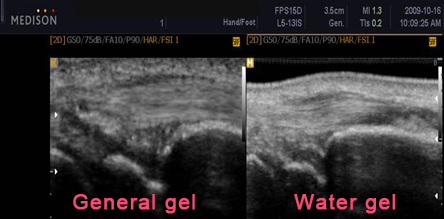

※ diagnostic imaging measures the actual screen (Madison, diagnostic imaging)

※ Water gel measured attenuation coefficient certification authority (measured). The major constituent body of WATER and similar.